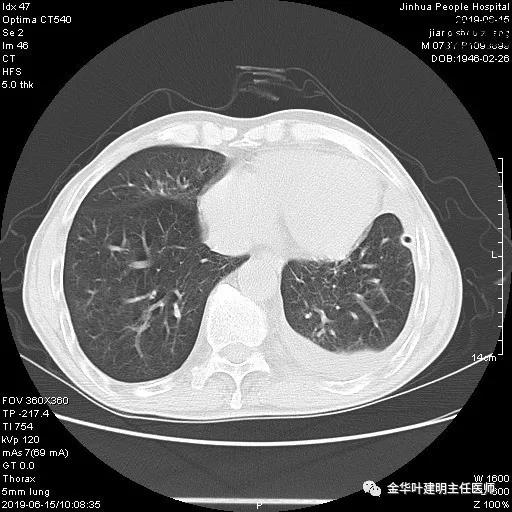

患者,男性,73岁,金华人。因“咳嗽咳痰伴胸闷2月,检查确诊左肺癌1周”入院。气管镜: 气管支气管内较多脓性分泌物,左肺上叶前段管腔新生物,局部活检、毛刷。气管镜病理:(左肺活检)鳞癌。阅胸部CT见左上叶开口处新生物,考虑需左上叶袖式切除及淋巴结清扫。具体CT表现如下:

6.15上午:24小时胸管引流出血性液250ml;复查胸部CT示: